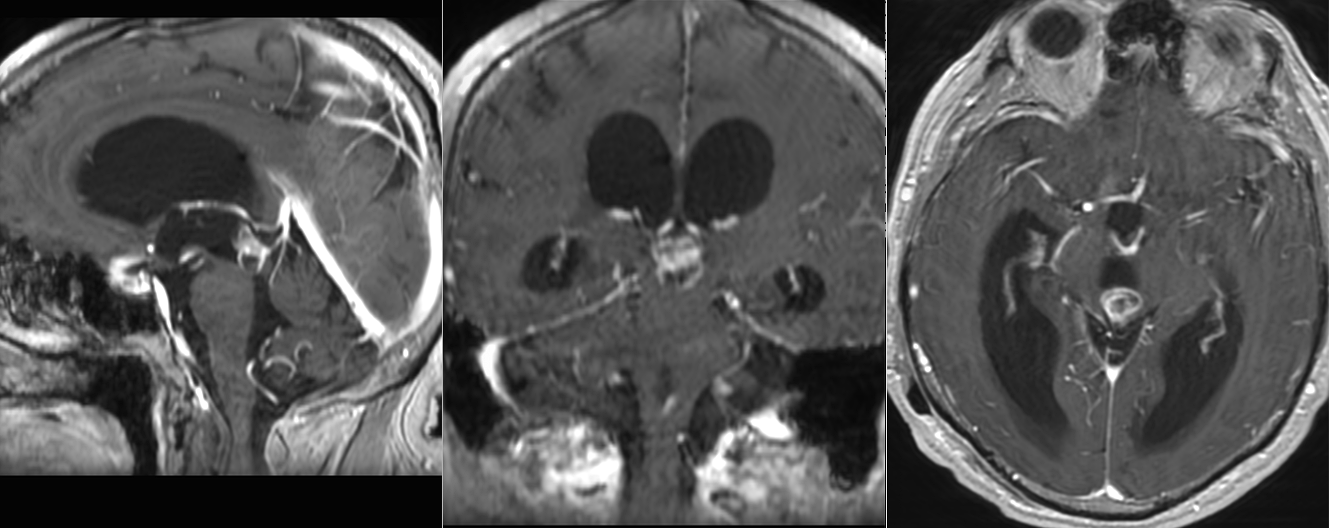

Tumoră gigantă de glandă pineală și sinus cavernos drept cu hidrocefalie – germinom malign

Tumoră de glandă pineală – hidrocefalie obstructivă

Tumoră de glandă pineală – hidrocefalie tratată prin drenaj ventriculo-peritoneal